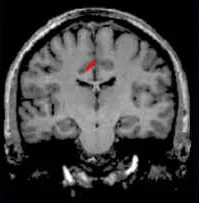

Slice Views

- Central sulcus = red

- Precentral sulcus = green

- Transverse-occipital = purple

- Postcentral sulcus = blue

- Intraparietal sulcus = yellow